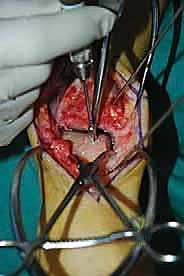

الغوص العميق في جراحة الطعم الخيفي الهيكلي (Structural Allograft Reconstruction)

يهدف هذا الإجراء العبقري إلى استبدال الغضروف والعظم التالفين والميتين بنسيج سليم تماماً مأخوذ من متبرع متوفى (طعم خيفي - Allograft). هذا الطعم يتم تعقيمه وحفظه في بنوك الأنسجة العالمية وفقاً لأعلى المعايير الطبية الصارمة لضمان خلوه من أي أمراض معدية والحفاظ على حيوية الخلايا الغضروفية.

- الترميم التشريحي الحقيقي: يسمح باستعادة الشكل الهندسي الدقيق لعظم الكاحل، بما في ذلك المنحنيات المعقدة لكتف التالوس.

- توفير غضروف طبيعي (Hyaline Cartilage): الغضروف المزروع هو غضروف زجاجي طبيعي،